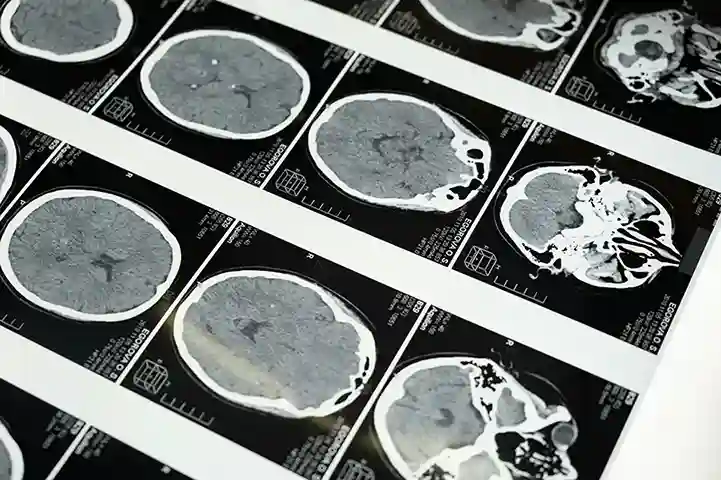

Sono Esperto in elettroencefalografia e valuto l’attività cerebrale anche in sonno o deprivazione ipnica, per un’analisi completa. La diagnostica precisa è la base di ogni terapia efficace

Integro la visita, dove necessario, con esami diagnostici specifici come l'EEG o indagini per immagini, avvalendomi di tecnologie affidabili. L'obiettivo è una diagnosi chiara, precisa e comprensibile.

Assolutamente Sì. Eseguo e referto personalmente gli EEG, anche in sonno spontaneo o dopo deprivazione, quando indicato. È uno strumento fondamentale per la diagnosi in neurologia, e preferisco occuparmene in prima persona.